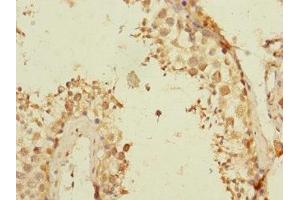

TEX43 anticorps (AA 1-134)

Aperçu rapide pour TEX43 anticorps (AA 1-134) (ABIN7171814)

- TEX43 Antibody